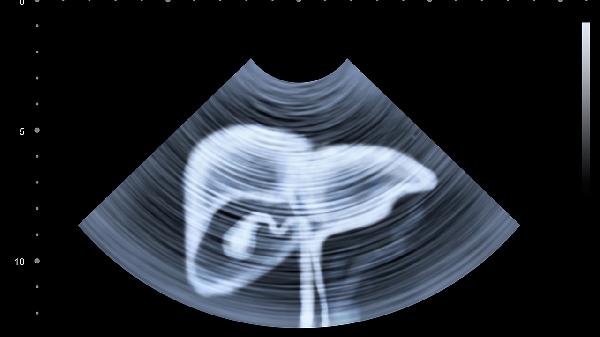

早期肝脏硬化可以治吗

早期肝硬化是可以治疗的,但需要根据具体病情进行评估。通常,早期肝硬化可能由于长期大量饮酒或病毒性肝炎等因素导致,患者可能会感到食欲减退、身体乏力,并伴有腹胀等症状。治疗的关键在于及时就医,并在医生指导下使用合适的药物或手术方法。